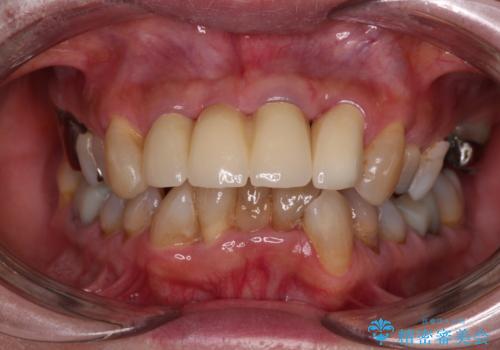

一番気になっていた隙間が埋まり、不快感から解放されました。